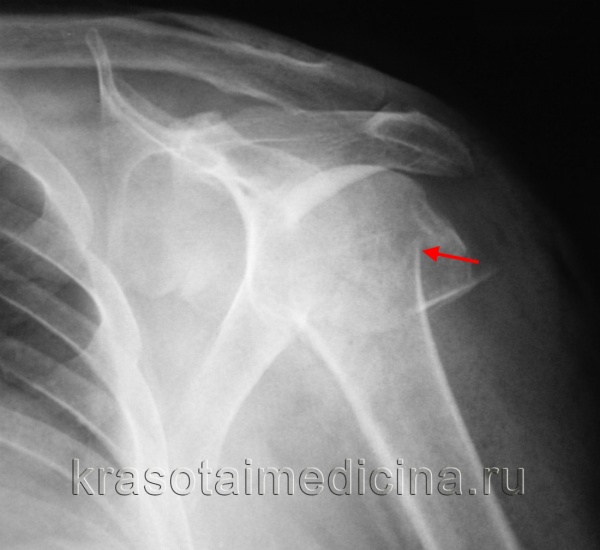

На представленных ниже рентгенограммах локтевого сустава определяется оскольчатый перелом мыщелков левого плеча с 4 большими фрагментами.

(Слева) На передне-задней рентгенограмме у пациента с ротированным переломом головки I типа определяется передне-задняя ротация суставной поверхности головки мыщелка плечевой кости. Данные в передне-задней проекции могут быть весьма скудными; часто единственной находкой является слабовыраженный контур нормальной суставной поверхности головки мыщелка плечевой кости.

(Справа) На боковой рентгенограмме у этою же пациента определяется передне-задняя ротация на 90° суставной поверхности головки мыщелка плечевой кости. Обратите внимание на приподнятые околосуставные жировые подушки, указывающие на гемартроз в результате острой травмы. (Слева) На сагиттальной 2D КТ с реформатированием определяется оскольчатый перелом головки мыщелка плечевой кости со смещением. Основной отломок часто смещается кпереди и может быть сильно ротирован. Кроме того, имеется перелом венечною и локтевого отростков.